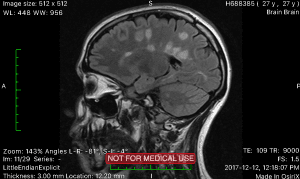

I’m 28 and living with Multiple Sclerosis. It’s hard for people who don’t have it to understand how much harder it is to get by each day with enough energy and positivity. It’s a daily challenge, and the challenges presented are different every day. I’m hoping to inspire others with MS to stay positive, to connect to others who have this disease, and to educate the world about how to help those with MS. I’ve also written a book of poetry about MS symptoms in the year 2017, when I had 3 major relapses and was very stressed. Hopefully others can use my work to remind themselves that they’re not alone in this battle.